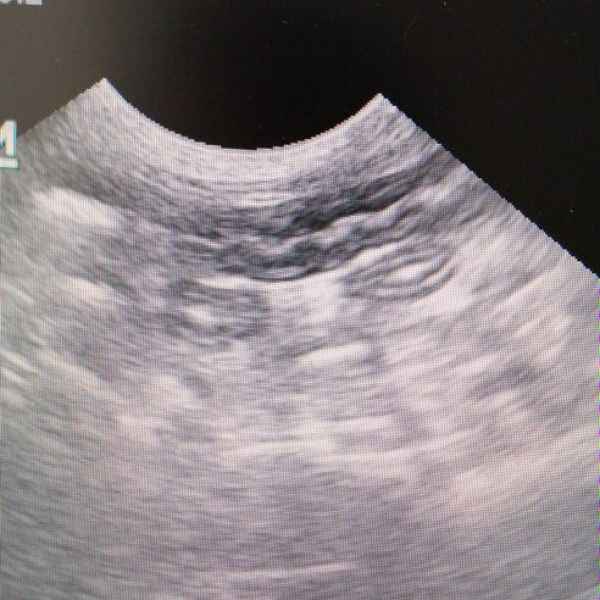

Знакомьтесь — это наш постоянный пациент Лосось. Конечно, ветеринарам хотелось бы встречаться с ним только на прививках. Но, увы, кот любит слопать что-нибудь совершенно несъедобное. Год назад ему уже делали две операции по извлечению инородных тел из кишечника. И вот опять хозяева рыжего вызвали бригаду врачей на дом. Лосось был в угнетённом состоянии. После УЗИ и анализов был поставлен диагноз: острое воспаление ЖКТ. К счастью, интенсивная терапия помогла, и кот полностью восстановился.

Кот Феликс, поступил с неукротимой рвотой, после проведения ультразвукового исследования был поставлен диагноз: линейное инородное тело в желудочно-кишечном тракте.Хирургами нашей клиники проведена операция по удалению инородного тела. Сейчас Феликс идет на поправку и близок к полному восстановлению.